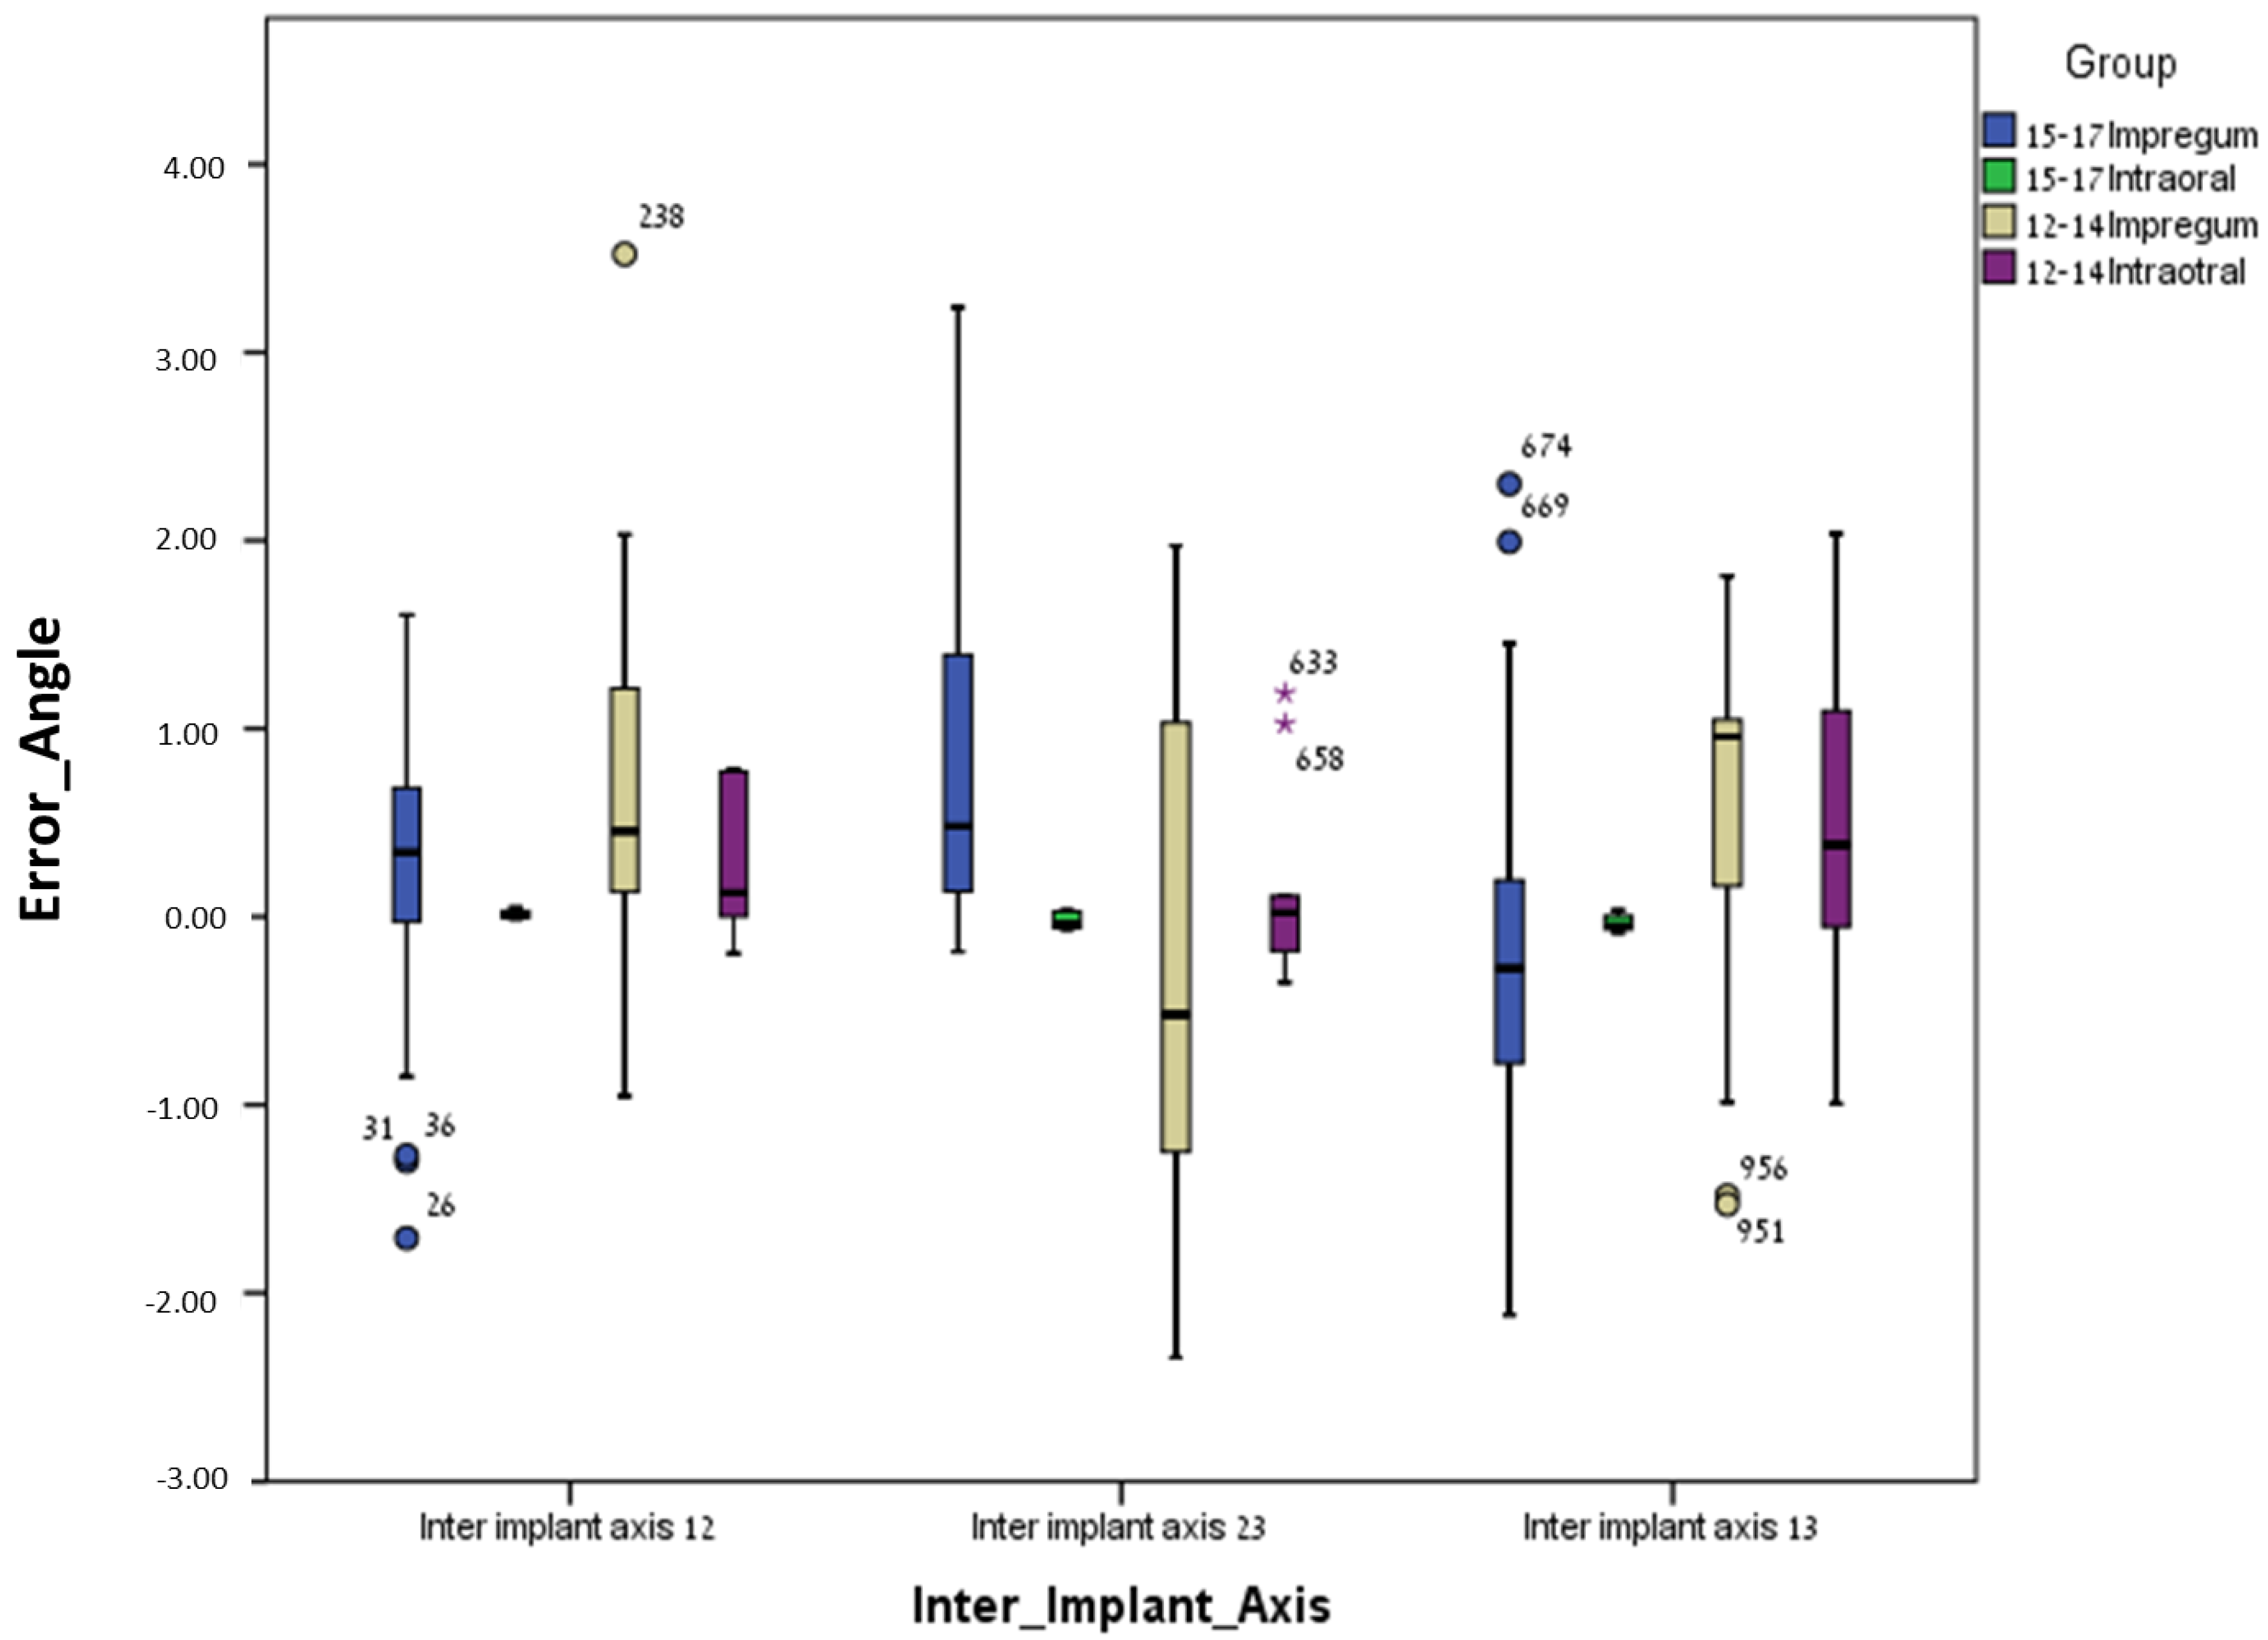

3. Results

3.1. Between Groups

3.2. Within Groups